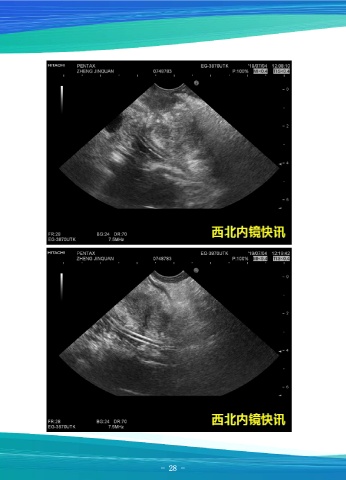

一例胆总管结石

患者女,52岁,因“上腹痛1月余”就诊,上腹部增强CT示:胆囊底部壁局限性增

厚并异常强化,考虑:胆囊腺肌症?黄色肉芽肿性胆囊炎?肿瘤性病变?;胆总管末端

异常强化小结节并低位胆道梗阻。